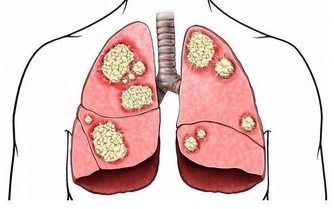

隨著癌細胞的轉移,前列腺癌患者會出現持續性的腰痛,還有會陰疼痛等。臥床時更為劇烈。

髖骨,胸腰椎是前列腺癌轉移的好發部位。常會有持續性,間歇性的疼痛,也有的人與有遊走的疼痛。